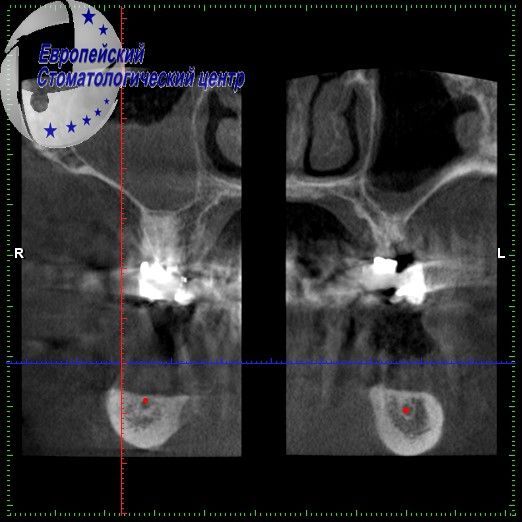

Ранее она установила импланты в другой клинике, но не согласившись с предложенным там планом лечения перед протезированием она обратилась в нашу клинику. Близость нижнечелюстного нерва существенно осложняла клиническую ситуацию для возможной доимплантации (см.Рис. 3). Было установлено дополнительно 4 импланта в обход нижнечелюстного нерва (см.Рис. 4-5).